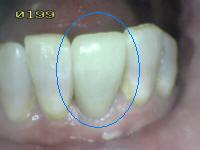

2. PERDIDA DE LA INTEGRIDAD DE LA SUPERFICIE

1. HALLAZGO: macha café con presencia de cavidad

1. CRITERIO DE DIAGNOSTICO: despues de secar por 5 sg, existe una pérdida de integridad superficial sin exposición de dentina

1. DIAGNOSTICO

1. ICDAS 3

2. TRATAMIENTO

1. operatoria

2. ACTIVIDAD

1. activa/detenida